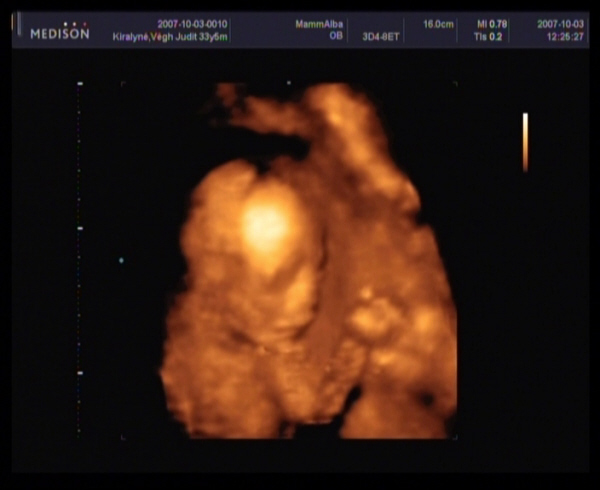

Megjöttem a 4D-ről.

Szupi volt, bár sajna kicsi bogaram állandóan vagy a néhlepénybe furta az arcát, vagy a kezecskéit tette az arcocskája elé, és elég nehéz volt rendesen elkapni.

Azt is mondta a doki, hogy nagyon mélyen fekszik, és ez is okozhatja azt, hogy ilyen későn kezdtem el érezni.

Amugy minden rendben van, 20 hetesnek megfelelő.

BPD - 4,97 CM

HC - 18,18 cm (ez nem tudom mi, de ez alapján 20+3 hetes)

FL - 3,10 CM

Átlagos magzatvíz, normális placenta, eltérés nem látható.

És végre a lábaközét is megmutatta nekünk.

Képek

Az első képen lehajtja a fejét, egy kicsit látszik a nózikája, ami meg az álla alatt van, az a köldökzsinór.